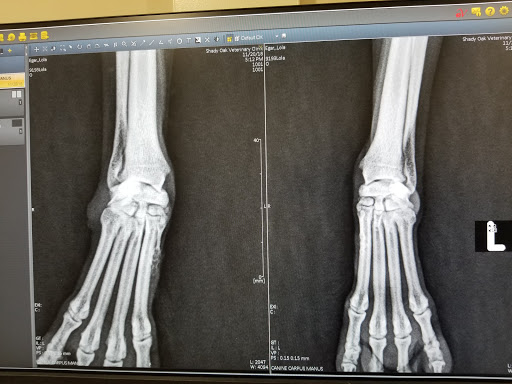

• Shady Oak Veterinary Clinic

Shady Oak Veterinary Clinic